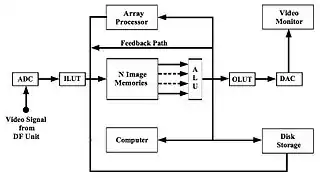

DSA Image Processor

- A block diagram of a DSA image processor is shown in Figure 7.6. It is seen that video signals from the XII-video image receptor are digitised using an analogue-to-digital converter (ADC) and the resulting digital data is passed through an Input Look-Up Table (ILUT) prior to storage in one of the image memories. The ILUT is generally used to logarithmically transform acquired images. It should be noted that in some system designs, logarithmic processing is performed using a look-up table between the image memory and the ALU so that displayed unsubtracted images appear in their conventional non-logarithmic format while subtracted images have the log transformation applied.

- At least three image memories are required for routine DSA - one for each of the mask and live images and the third for the subtracted image, although most systems have the capacity for storing more than three images. Image subtraction is performed using an arithmetic/logic unit (ALU) with the subtracted image data being fed along the Feedback Path so that it can be stored in image memory. The ALU can also be used for averaging images for noise reduction purposes.

- The type of image processor shown in the figure can also be used to implement a number of variations on the basic theme of DSA imaging. One of these variations is referred to as Time- Interval-Difference (TID) Imaging, which involves periodically updating the contents of the mask image memory during the DSA study. This approach allows short-term changes between images to be displayed and therefore lends itself to imaging fast moving events, such as cardiac contractions.

- A second variation on the theme involves acquiring images of both the arterial and the venous vessels in the same region of the patient (e.g. the carotid arteries and jugular veins in the neck) so that when a mask image in the arterial phase is subtracted from a live image from the venous phase, a subtracted image showing both arterial and venous vessels can be generated. A third variation is referred to as Roadmapping - see Figure 7.7 - where an image at peak opacification is used as a mask and subsequent subtraction images, without injection of additional contrast medium, are used to guide advancement of a catheter or guide-wire.